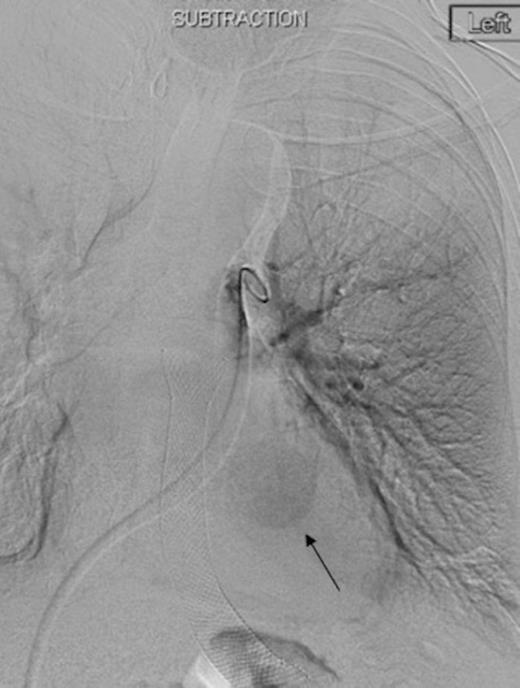

Coronal CT image in arterial phase demonstrating a 28mm diameter left lower lobe pulmonary artery aneurysm in association with a fluid collection

Three days later he presented with significant haemoptysis. A CT pulmonary angiogram (CTPA) demonstrated an increase in size of the PAA from 14mm to 28mm (Figure 1) diameter. A radiology opinion was sought and the patient transferred to the angio-suite for intervention.